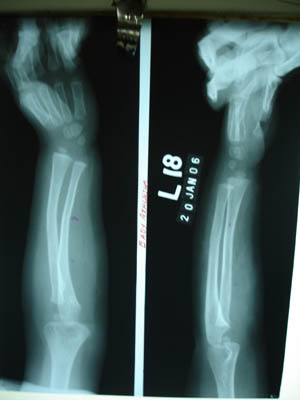

Colles’ fracture 2

Colles' fracture 2